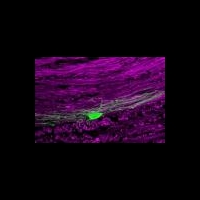

Разработанный учеными метод генной терапии стимулирует дифференцировку имеющихся в ткани мозга стволовых клеток и клеток-предшественников в олигодендроциты за счет повышения продукции белка LIF – фактора, ингибирующего лейкемию (leukemia inhibitory factor). Результаты более ранних работ на мышиных моделях показали, что этот белок, естественным образом синтезирующийся в организме, способствует самообновлению нервных стволовых клеток и подавляет разрушающие миелин иммунные реакции.

По словам профессора Паттерсона, уникальность работы заключается в том, что местное введение генотерапевтических векторов обеспечивало синтез терапевтического белка, а, соответственно, и восстановление миелина только в тканях мозга. Он также отмечает, что подобный подход позволяет избежать возможных побочных эффектов, связанных с введением генотерапевтического препарата в кровоток. На мышиной модели описанный метод стимулировал пролиферацию клеток-предшественников и их дифференцировку в синтезирующие миелин зрелые олигодендроциты. При этом количество зрелых олигодендроцитов после терапии достигало показателей, характерных для здоровых животных.